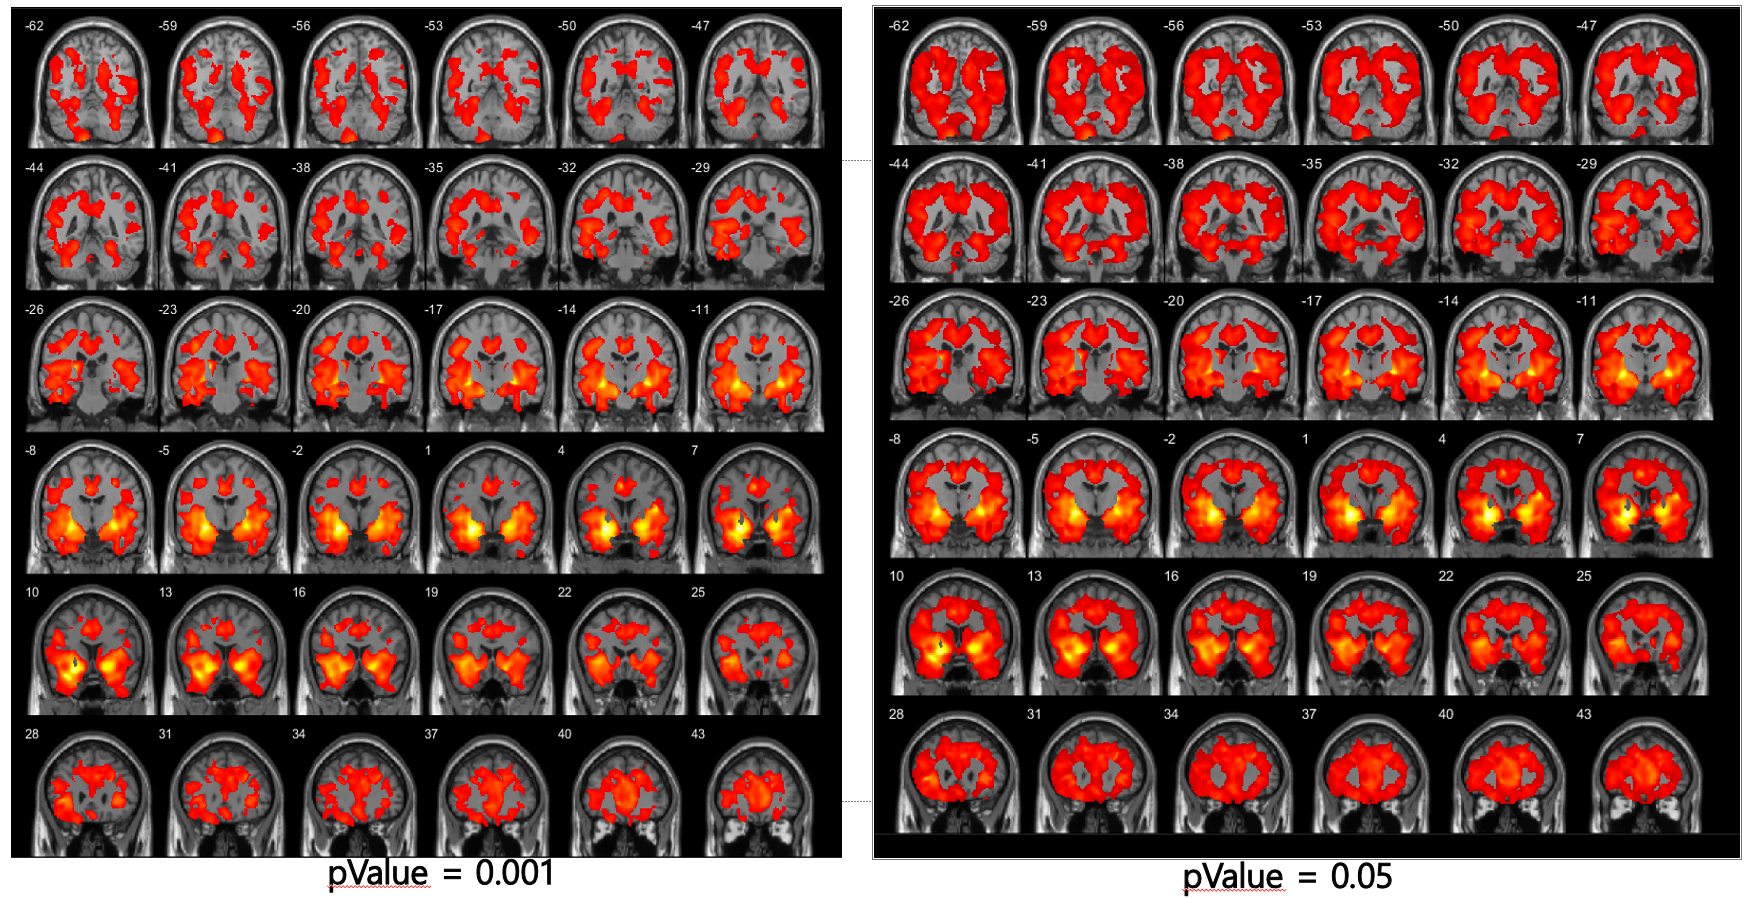

MRI Image Analysis